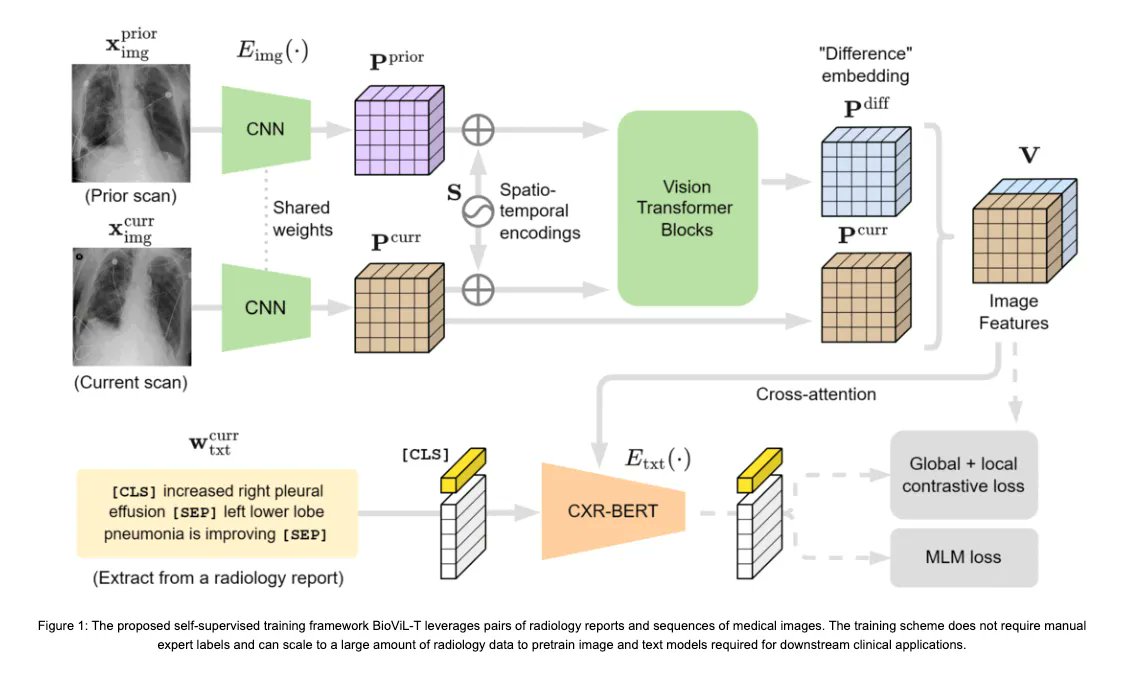

Nice work by @ozanoktay__, @MSFTResearch, & @mattlungrenMD on #medical vision-language processing by incorporating one dimension often neglected in #ImagingAI: time. Post 👉 buff.ly/3JmdaE5 Talk 👉 buff.ly/3XejwuZ Models 👉 buff.ly/3JqLDRP